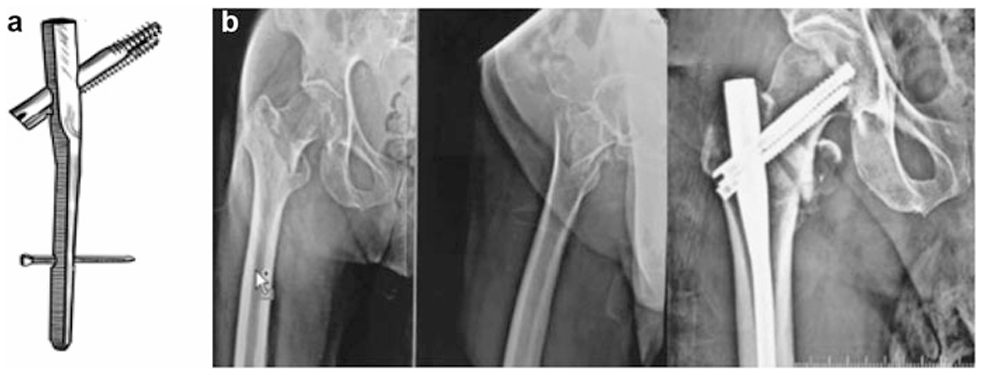

股骨近端钉(PFN)

AO/ASIF于1996年推出,认为单枚拉力螺钉无法抵抗股骨近端应力且缺乏旋转稳定性。PFN长24cm,近端直径17mm(后改为15.5mm以适应亚洲人群),用于稳定和不稳定转子间骨折,分长(36-42mm)、标准(24mm)和短钉(18mm)三种(图13)。

图13 (a) AO/ASIF股骨近端髓内钉示意图;(b) 亚洲型股骨近端髓内钉实物图;(c) 术前与术后X光片对比,显示标准股骨近端髓内钉(PFN)固定(24厘米长度);(d) 术前与术后X光片对比,显示短型股骨近端髓内钉(PFN)固定(18厘米长度)

其优势在于6.5mm防旋钉可提供额外旋转稳定性,远端渐细设计分散应力,降低股骨干骨折风险。但存在螺钉退出、Z效应和反向Z效应等并发症。